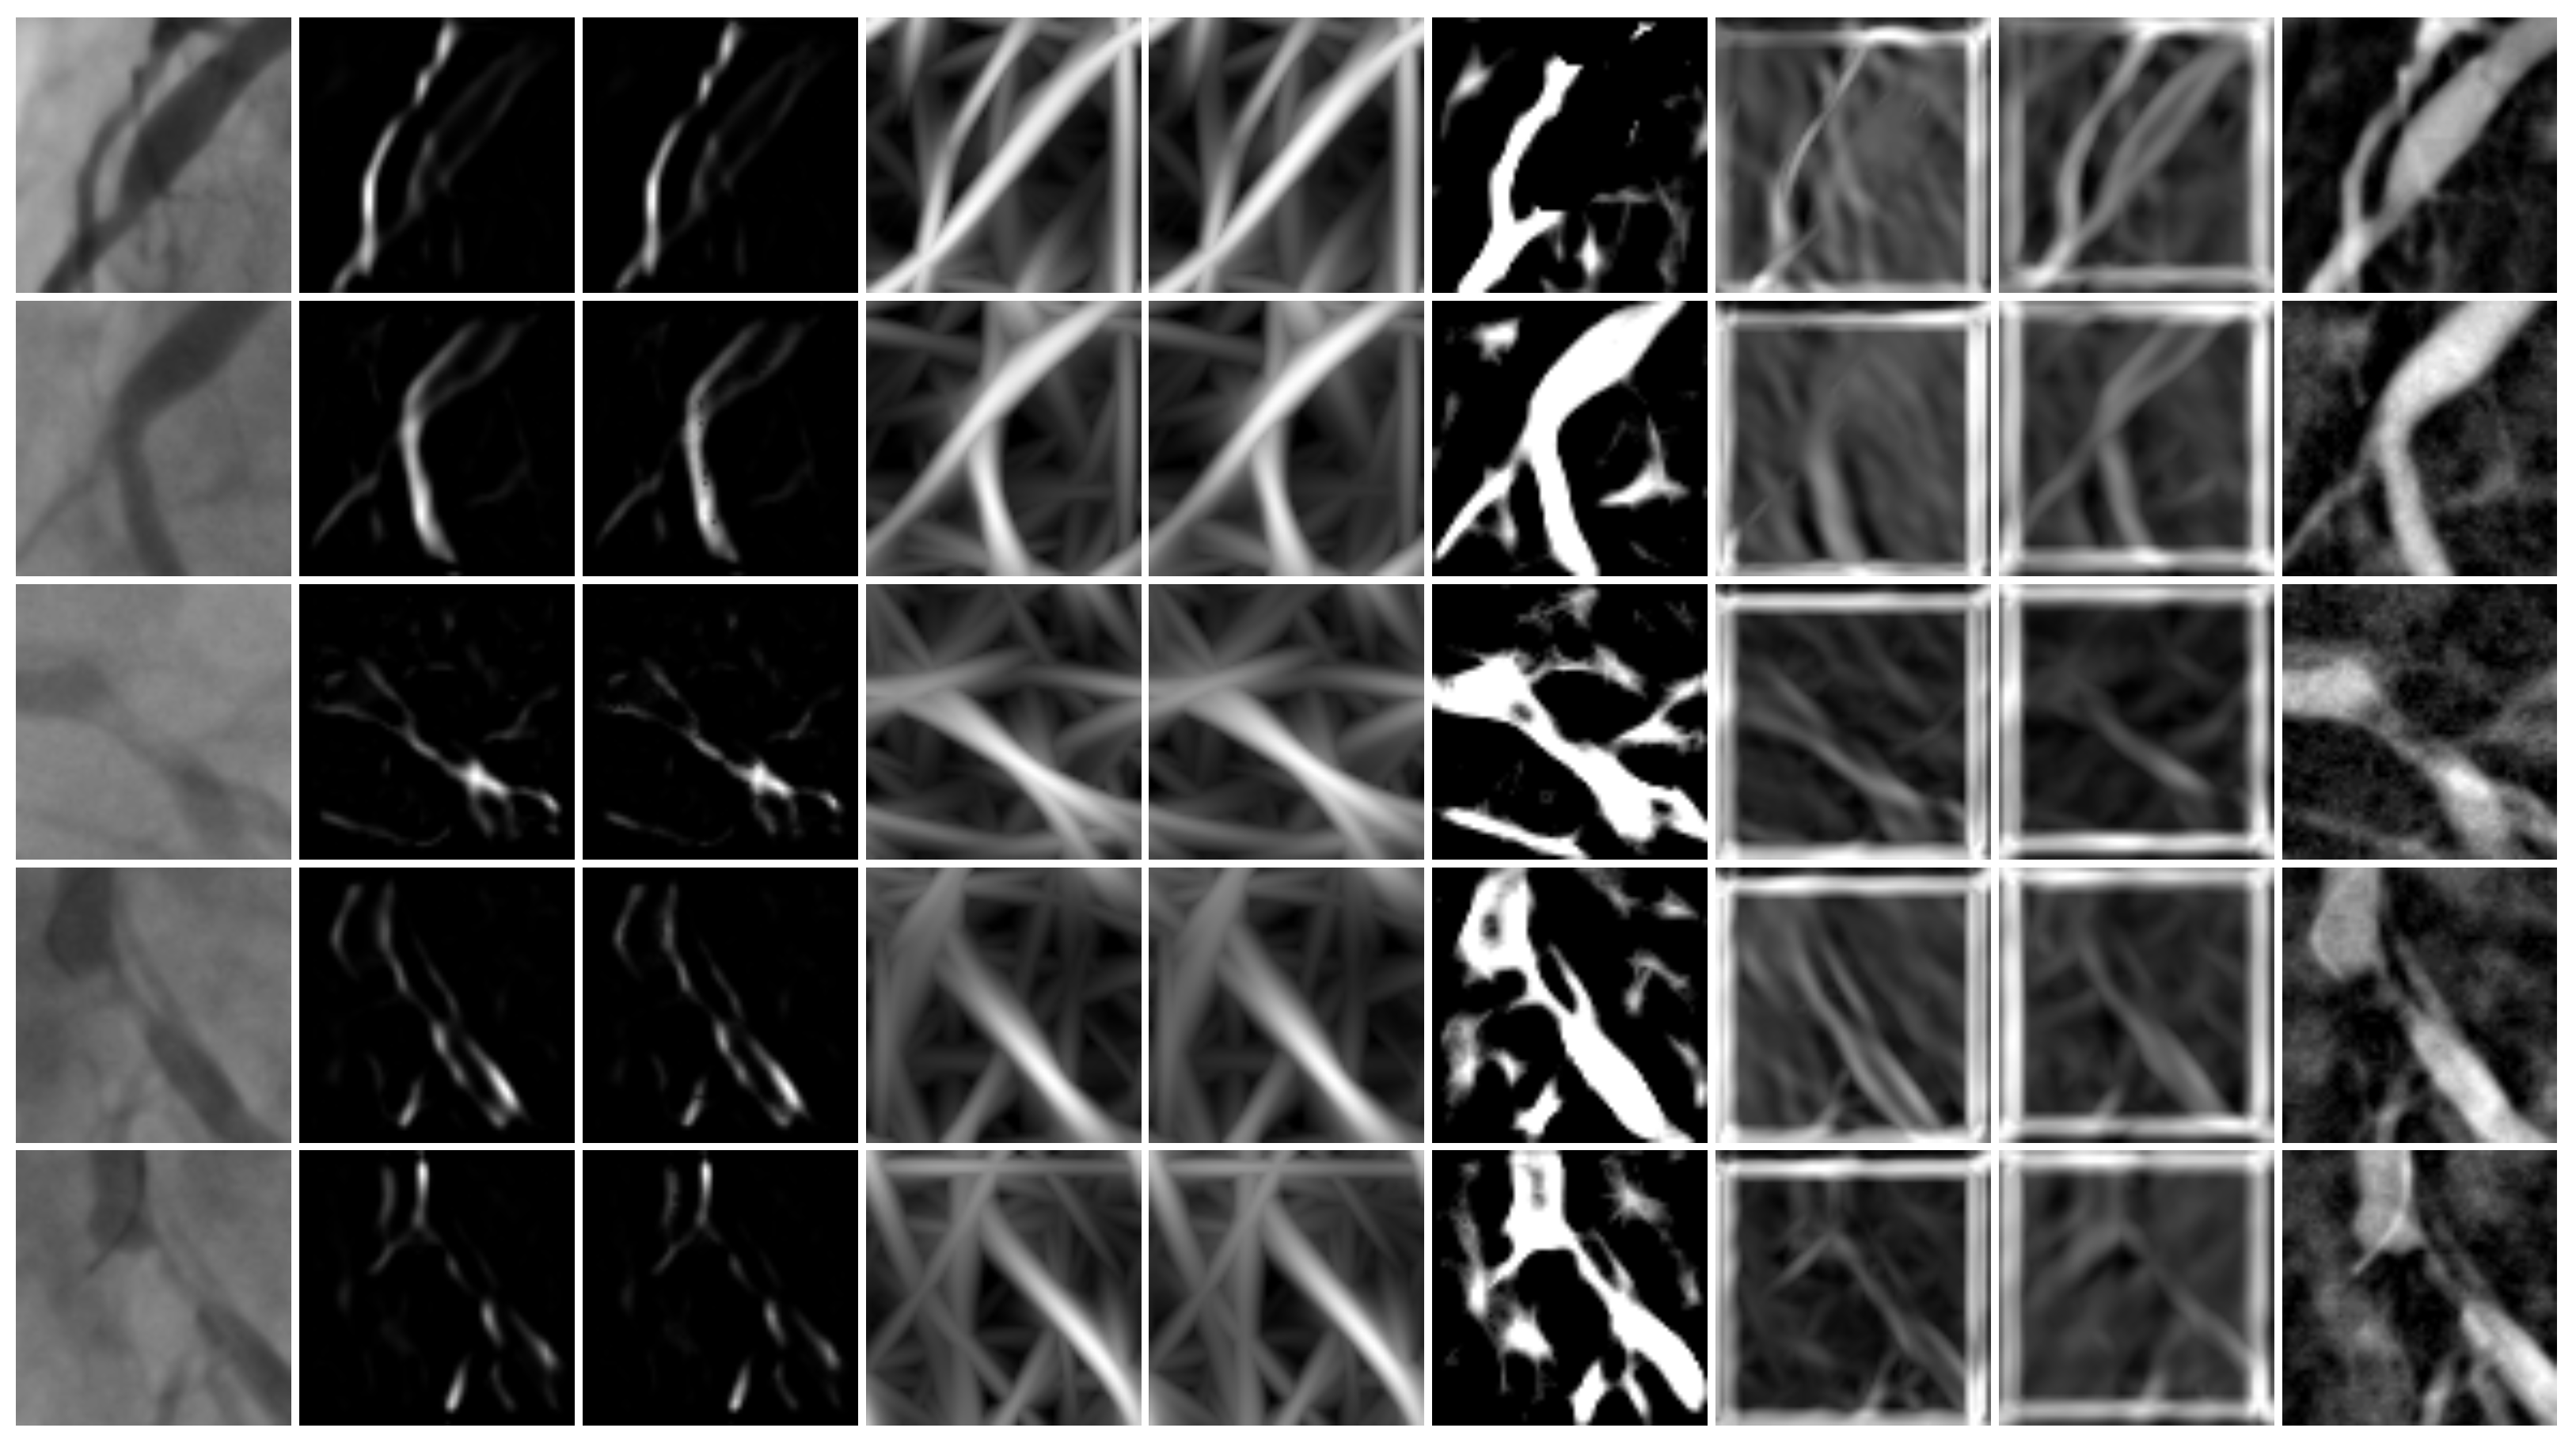

- Development of a feature vector consisting of 473 distinct features extracted from the original images and responses from vessel enhancement filters.

2.1. Feature Extraction